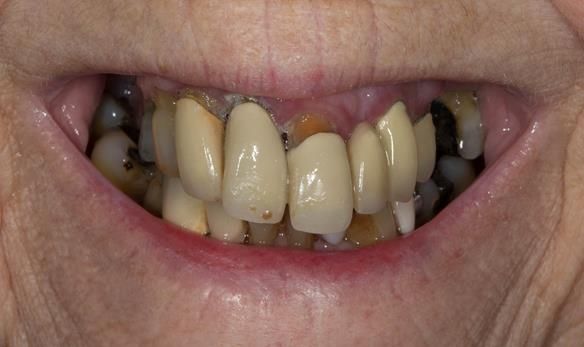

This 73 year old woman was referred to me by her general dental practiioner for treatment.

- “Upper teeth/crowns/bridges all loose”

- “Dentures seem the only option”

- “Bottom teeth are not good but still functional”

- The remaining natural upper natural teeth and lower back molars were heavily restored having generalised periodontitis stage 4 Grade C. Some of the teeth exhibited caries. The prognosis for these teeth ranged from dubious to hopeless.

- The lower teeth (apart from the lower back molars) had better progniosis and were to be managed by the referring general dental practitioner.

- The upper and lower acrylic based partial dentures exhibited suboptimal extension of the flanges and saddles. They had poor retention, support, stability and tissue fit.

- The patient had a high smile line showing 5mm or more alveolar soft tissue above the upper front teeth during social interaction.